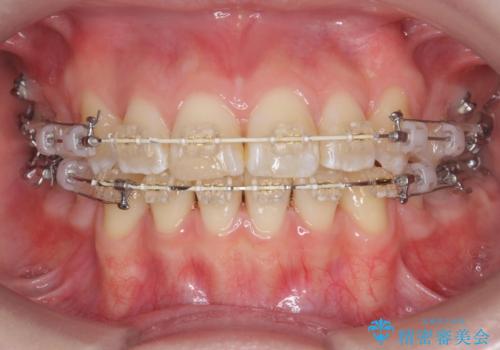

- 矯正装置

- ワイヤー矯正

- 2年8ヶ月

前歯の角度を改善するために小臼歯4本の抜歯を行いワイヤー マルチブラケットを用いて、しっかりと前歯の角度を改善する治療計画としました。

綺麗な歯並びを手に入れられたと同時に、口元もスッキリし、仕上がりに満足いただくことができました。